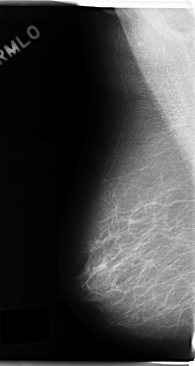

C_0185_1.RIGHT_CC

RIGHT_CC LINES 4720 PIXELS_PER_LINE 2544 BITS_PER_PIXEL 12 RESOLUTION 50 NON_OVERLAY

FILE: C_0185_1.LEFT_CC.OVERLAY

TOTAL_ABNORMALITIES 1

ABNORMALITY 1

LESION_TYPE MASS SHAPE LOBULATED MARGINS MICROLOBULATED

ASSESSMENT 5

SUBTLETY 5

PATHOLOGY MALIGNANT

TOTAL_OUTLINES 1

BOUNDARY